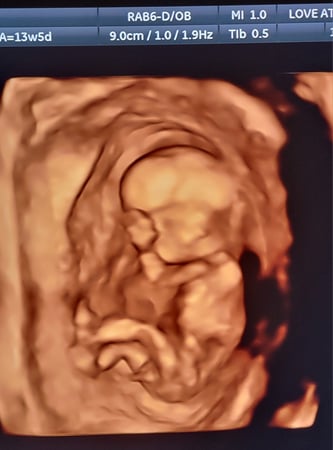

Tasha Crump, is registered by the American Registry of Diagnostic Medical Sonographers (ARDMS) and have over 18 years experience in medical diagnostic sonography specializing in Maternal Fetal Medicine. She is a highly proficient in the art of 3D 4D ultrasound. Tasha has practiced and trained in NYC's top ranked hospitals including Columbia Presbyterian. At Love at First Sight Imaging Studio you'll be in a very comfortable and calming atmosphere for you and your family to bond with your baby. We have state of the art equipment with HD Live to image unbelievably realistic views of your baby. You will fall in Love at First Sight.